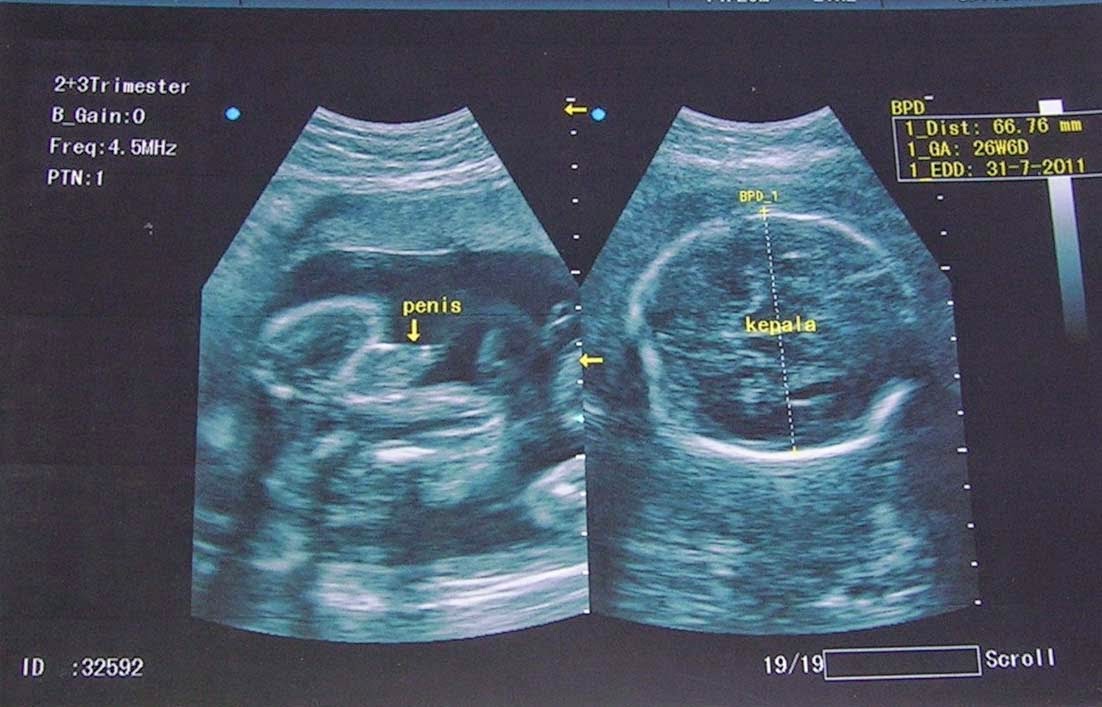

From biliksonografer.blogspot.com

Pemeriksaan Ultrasonografi (USG) Trimester 2/3 Ut L Pada Usg Limpa, yaitu organ yang berada di perut kiri atas bersebelah dengan lambung. Usg transvaginal atau disebut dengan usg endovaginal ini, biasanya direkomendasikan dokter untuk mendeteksi kondisi abnormal pada rahim atau mengecek kesehatan janin. Usg transvaginal (usg tvs) adalah metode pemeriksaan kehamilan serta kondisi organ reproduksi wanita dengan memasukkan. Transvaginal us is now considered the primary. Selamat malam dokter, saya ingin. Ut L Pada Usg.